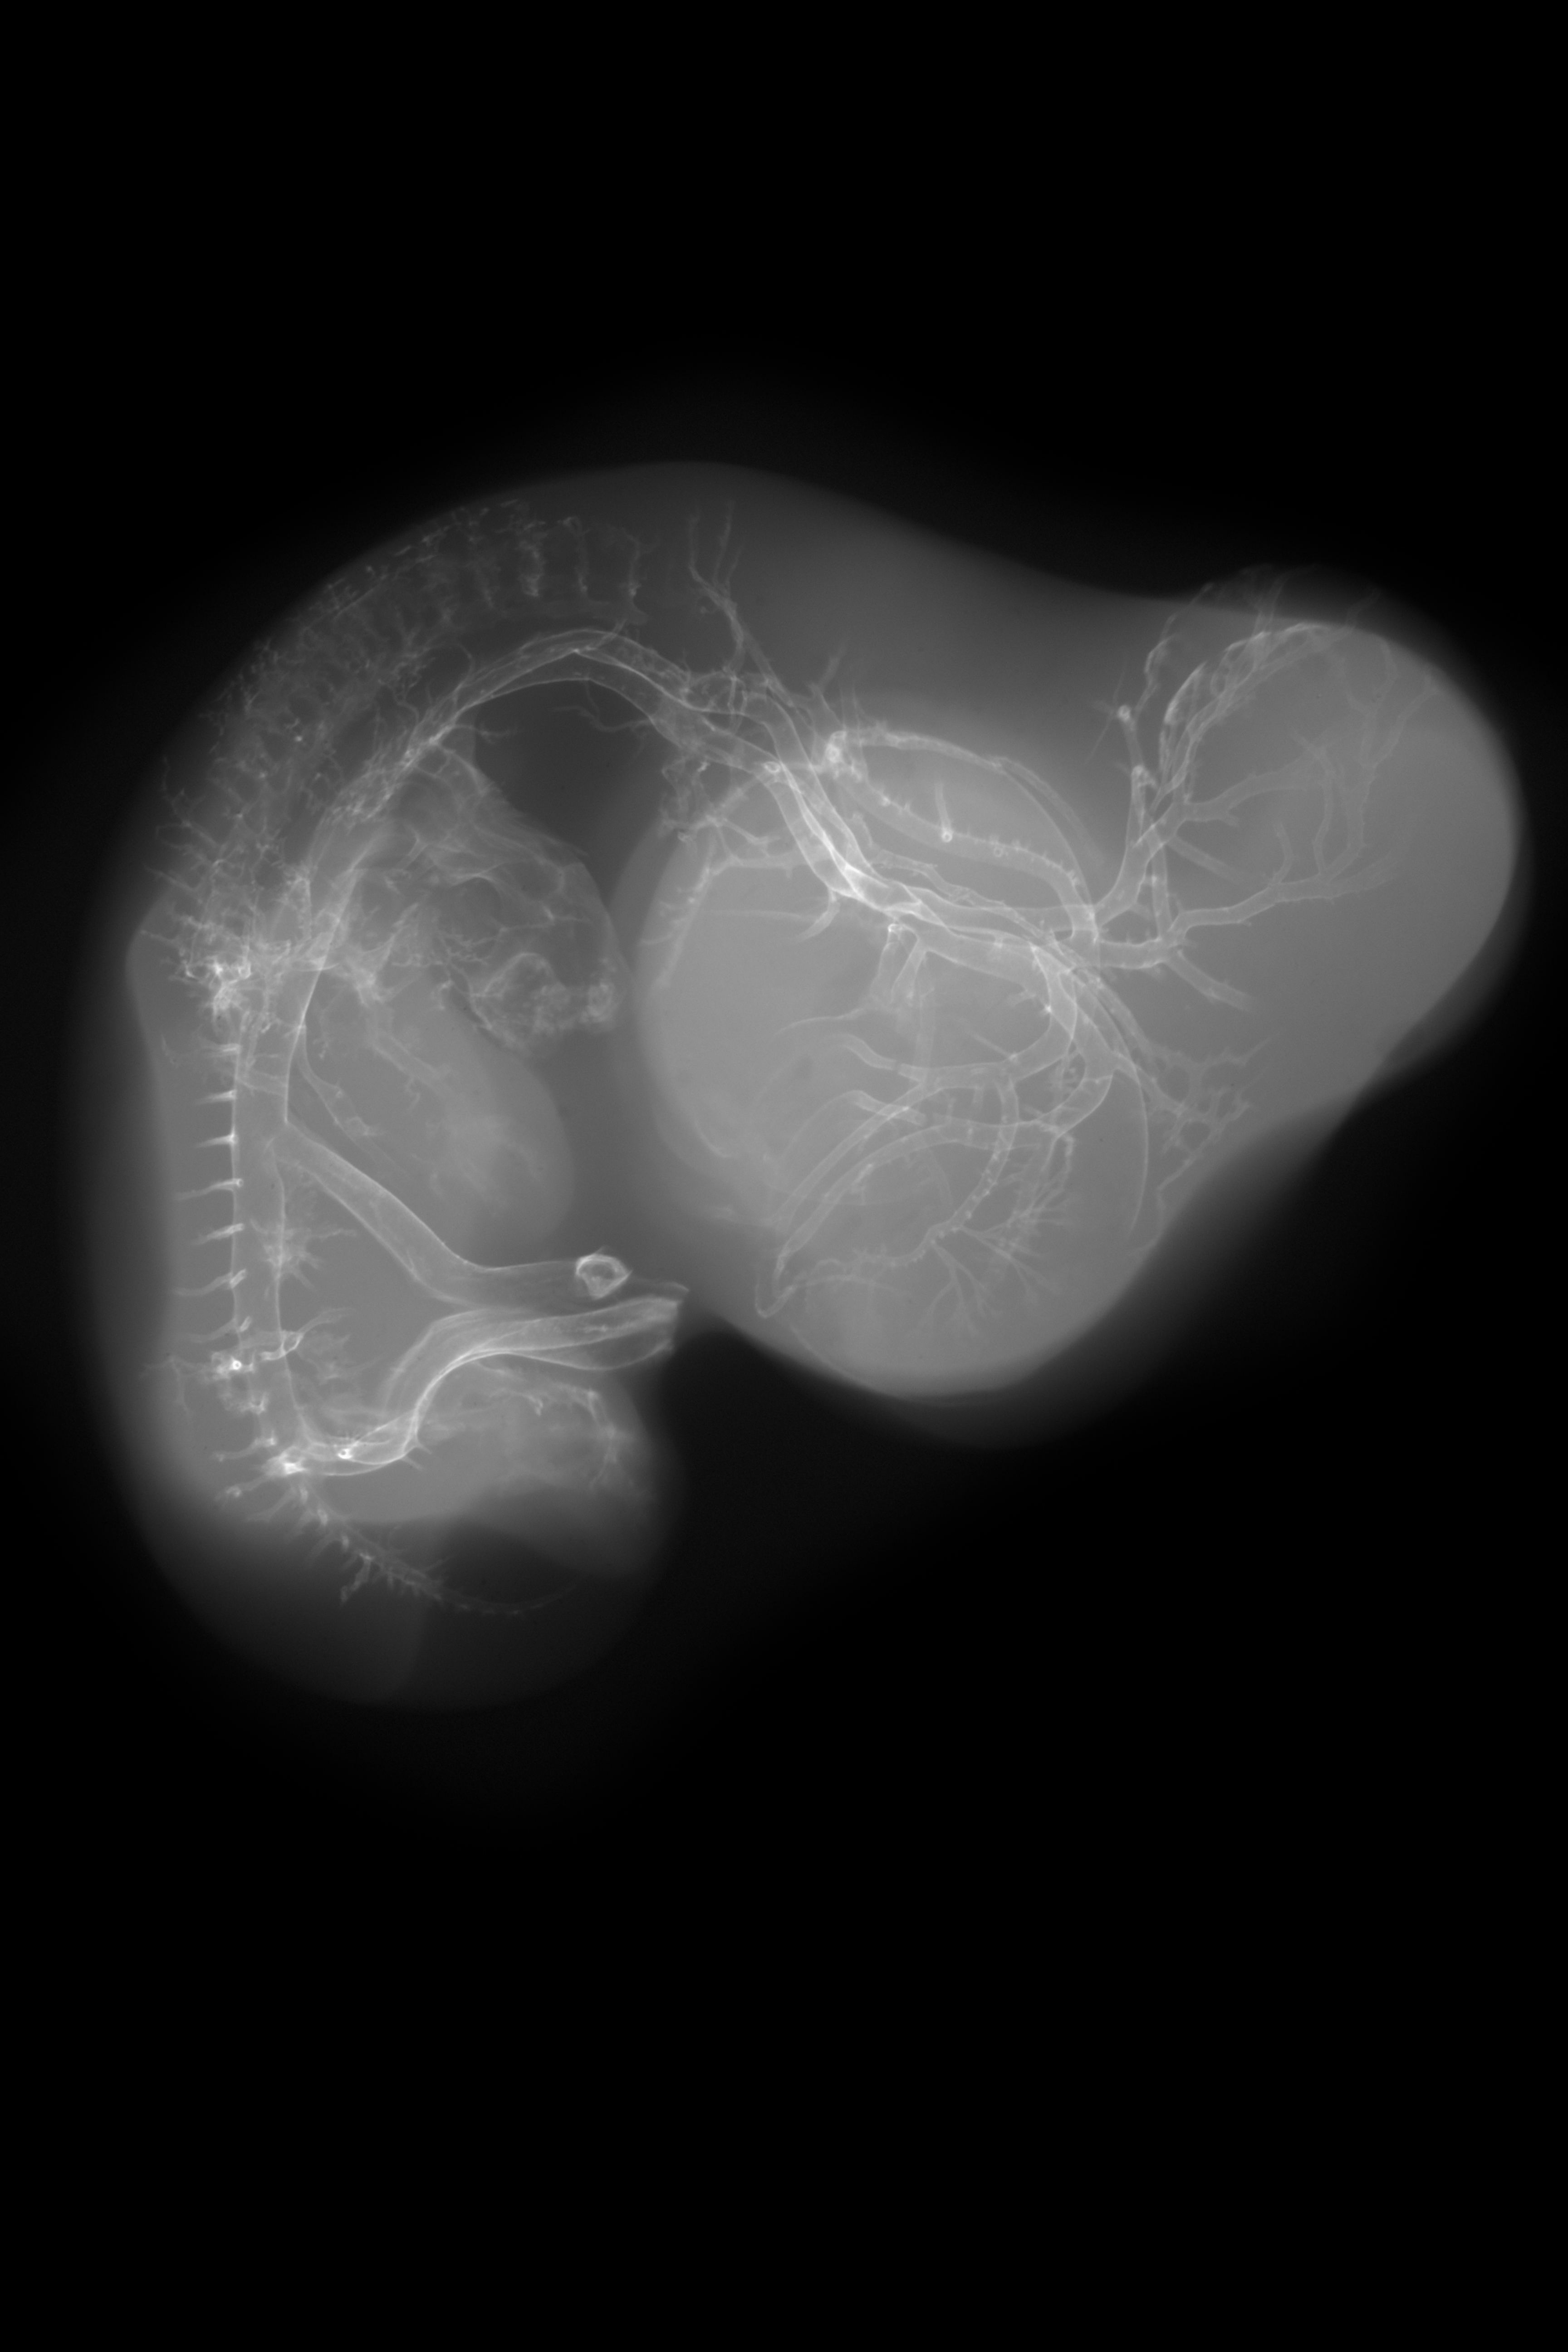

Chick Embryo Microangiography

Hamburger-Hamilton (HH) Stage 28 (approx. 5.5 - 6 days)

X-Ray Micrographs